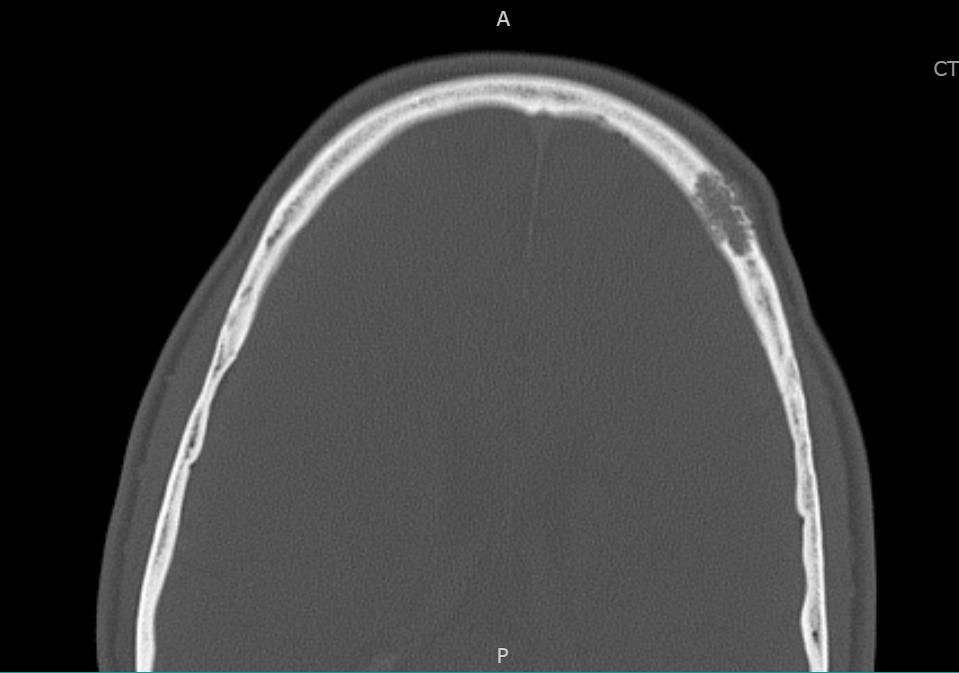

Radiolucency in frontal bone sagittal + axial CT. Here’s a clue: Keep a low power impression Mild expansive remodeling, cortical thinning, radial (spoke) trabecular bone radiating around a central lucency Diagnosis? John Reith Shivani Ahlawat Laura Fayad Lisa Rooper